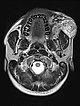

Axiale, T2-gewichtete MRT auf Höhe der Wange zeigt die AVM relativ hyperintens mit Ödem des Gewebes und Ausdehnung bis zum linken Unterkiefer. Im rostralen Abschnitt auch einige schwarze flow-voids durch stark durchblutete Arterien innerhalb der AVM.